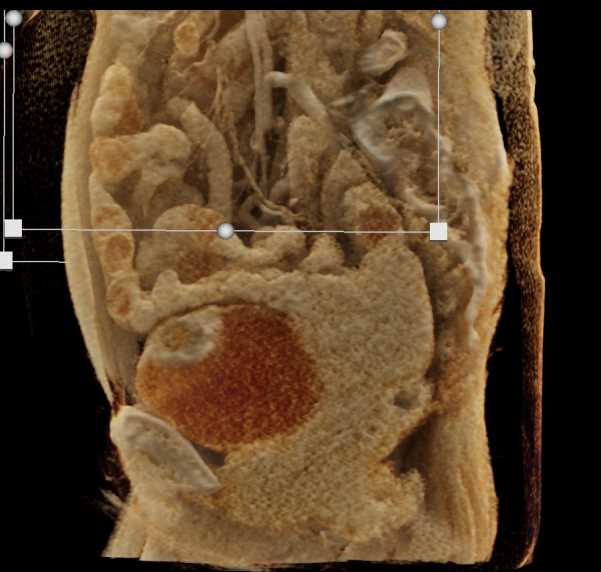

Urachal Carcinoma of the Bladder